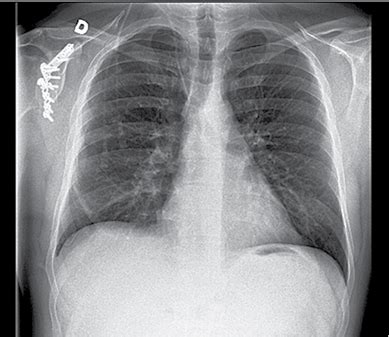

Tikslesnei diagnozei nustatyti gali būti atliekami įvairūs laboratoriniai ir instrumentiniai tyrimai. Pirmasis žingsnis dažnai yra krūtinės ląstos rentgenograma, kuri leidžia įvertinti uždegimo lokalizaciją, dydį ir pobūdį. Jei situacija sudėtingesnė, gali būti atliekama kompiuterinė tomografija, kuri pateikia detalesnį plaučių vaizdą. Kraujo tyrimai - atliekami siekiant įvertinti uždegimą ir nustatyti infekcijos pobūdį. Sergant plaučių uždegimu nustatomas padidėjęs leukocitų kiekis, aptinkama toksinių granuliocitų, padidėja eritrocitų nusėdimo greitis, taip pat C reaktyvinio baltymo (CRB) koncentracija kraujo serume.